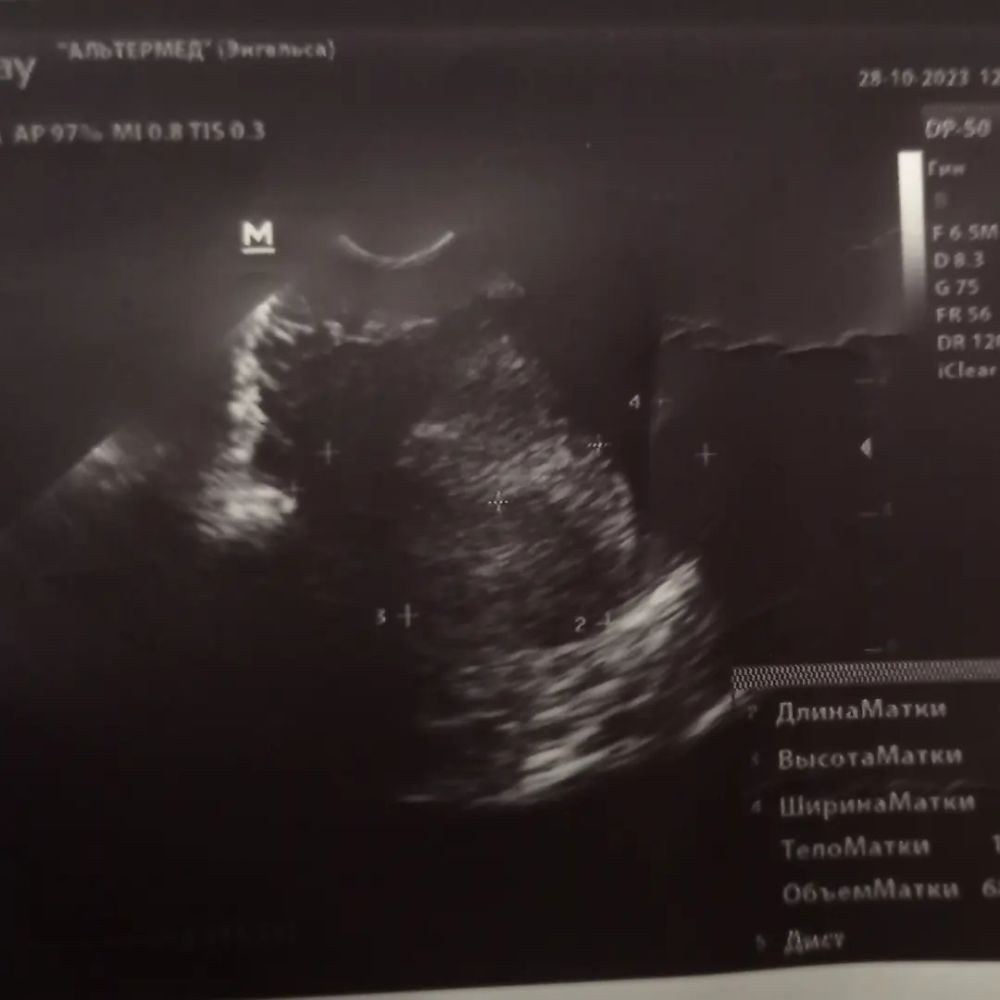

В субботу была на УЗИ платно

Всё хорошо, рановато пришла конечно, зато спокойно задала всё интересующие вопросы, услышала благоприятные прогнозы, назначили повторное УЗИ на 8 число. Со слов гинеколога там уже всё будет 😍

Прикрепляю УЗИ